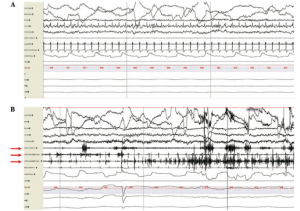

This week I continued learning about REM sleep behavioral disorder. As I mentioned before, REM sleep behavioral disorder (RBD) is the enactment of dreams during REM sleep. Approximately 0.5% of the general population is affected by RBD, the majority occurring in men. In order to be diagnosed with RBD a patient must (1) have dream enactment and (2) REM sleep without atonia (RSWA) as illustrated on the polysomnograph. Typically, patients with RBD have over 25% RSWA. In the lab, we are learning how to quantify RSWA by scoring muscle movements that occur in the chin, leg, and arm during REM sleep. The polysomnograph is divided into 30-second epochs, where we score phasic and tonic muscle activity. One of the aims of this study is to determine whether the amount of RSWA varies to the underlying causation of RBD.